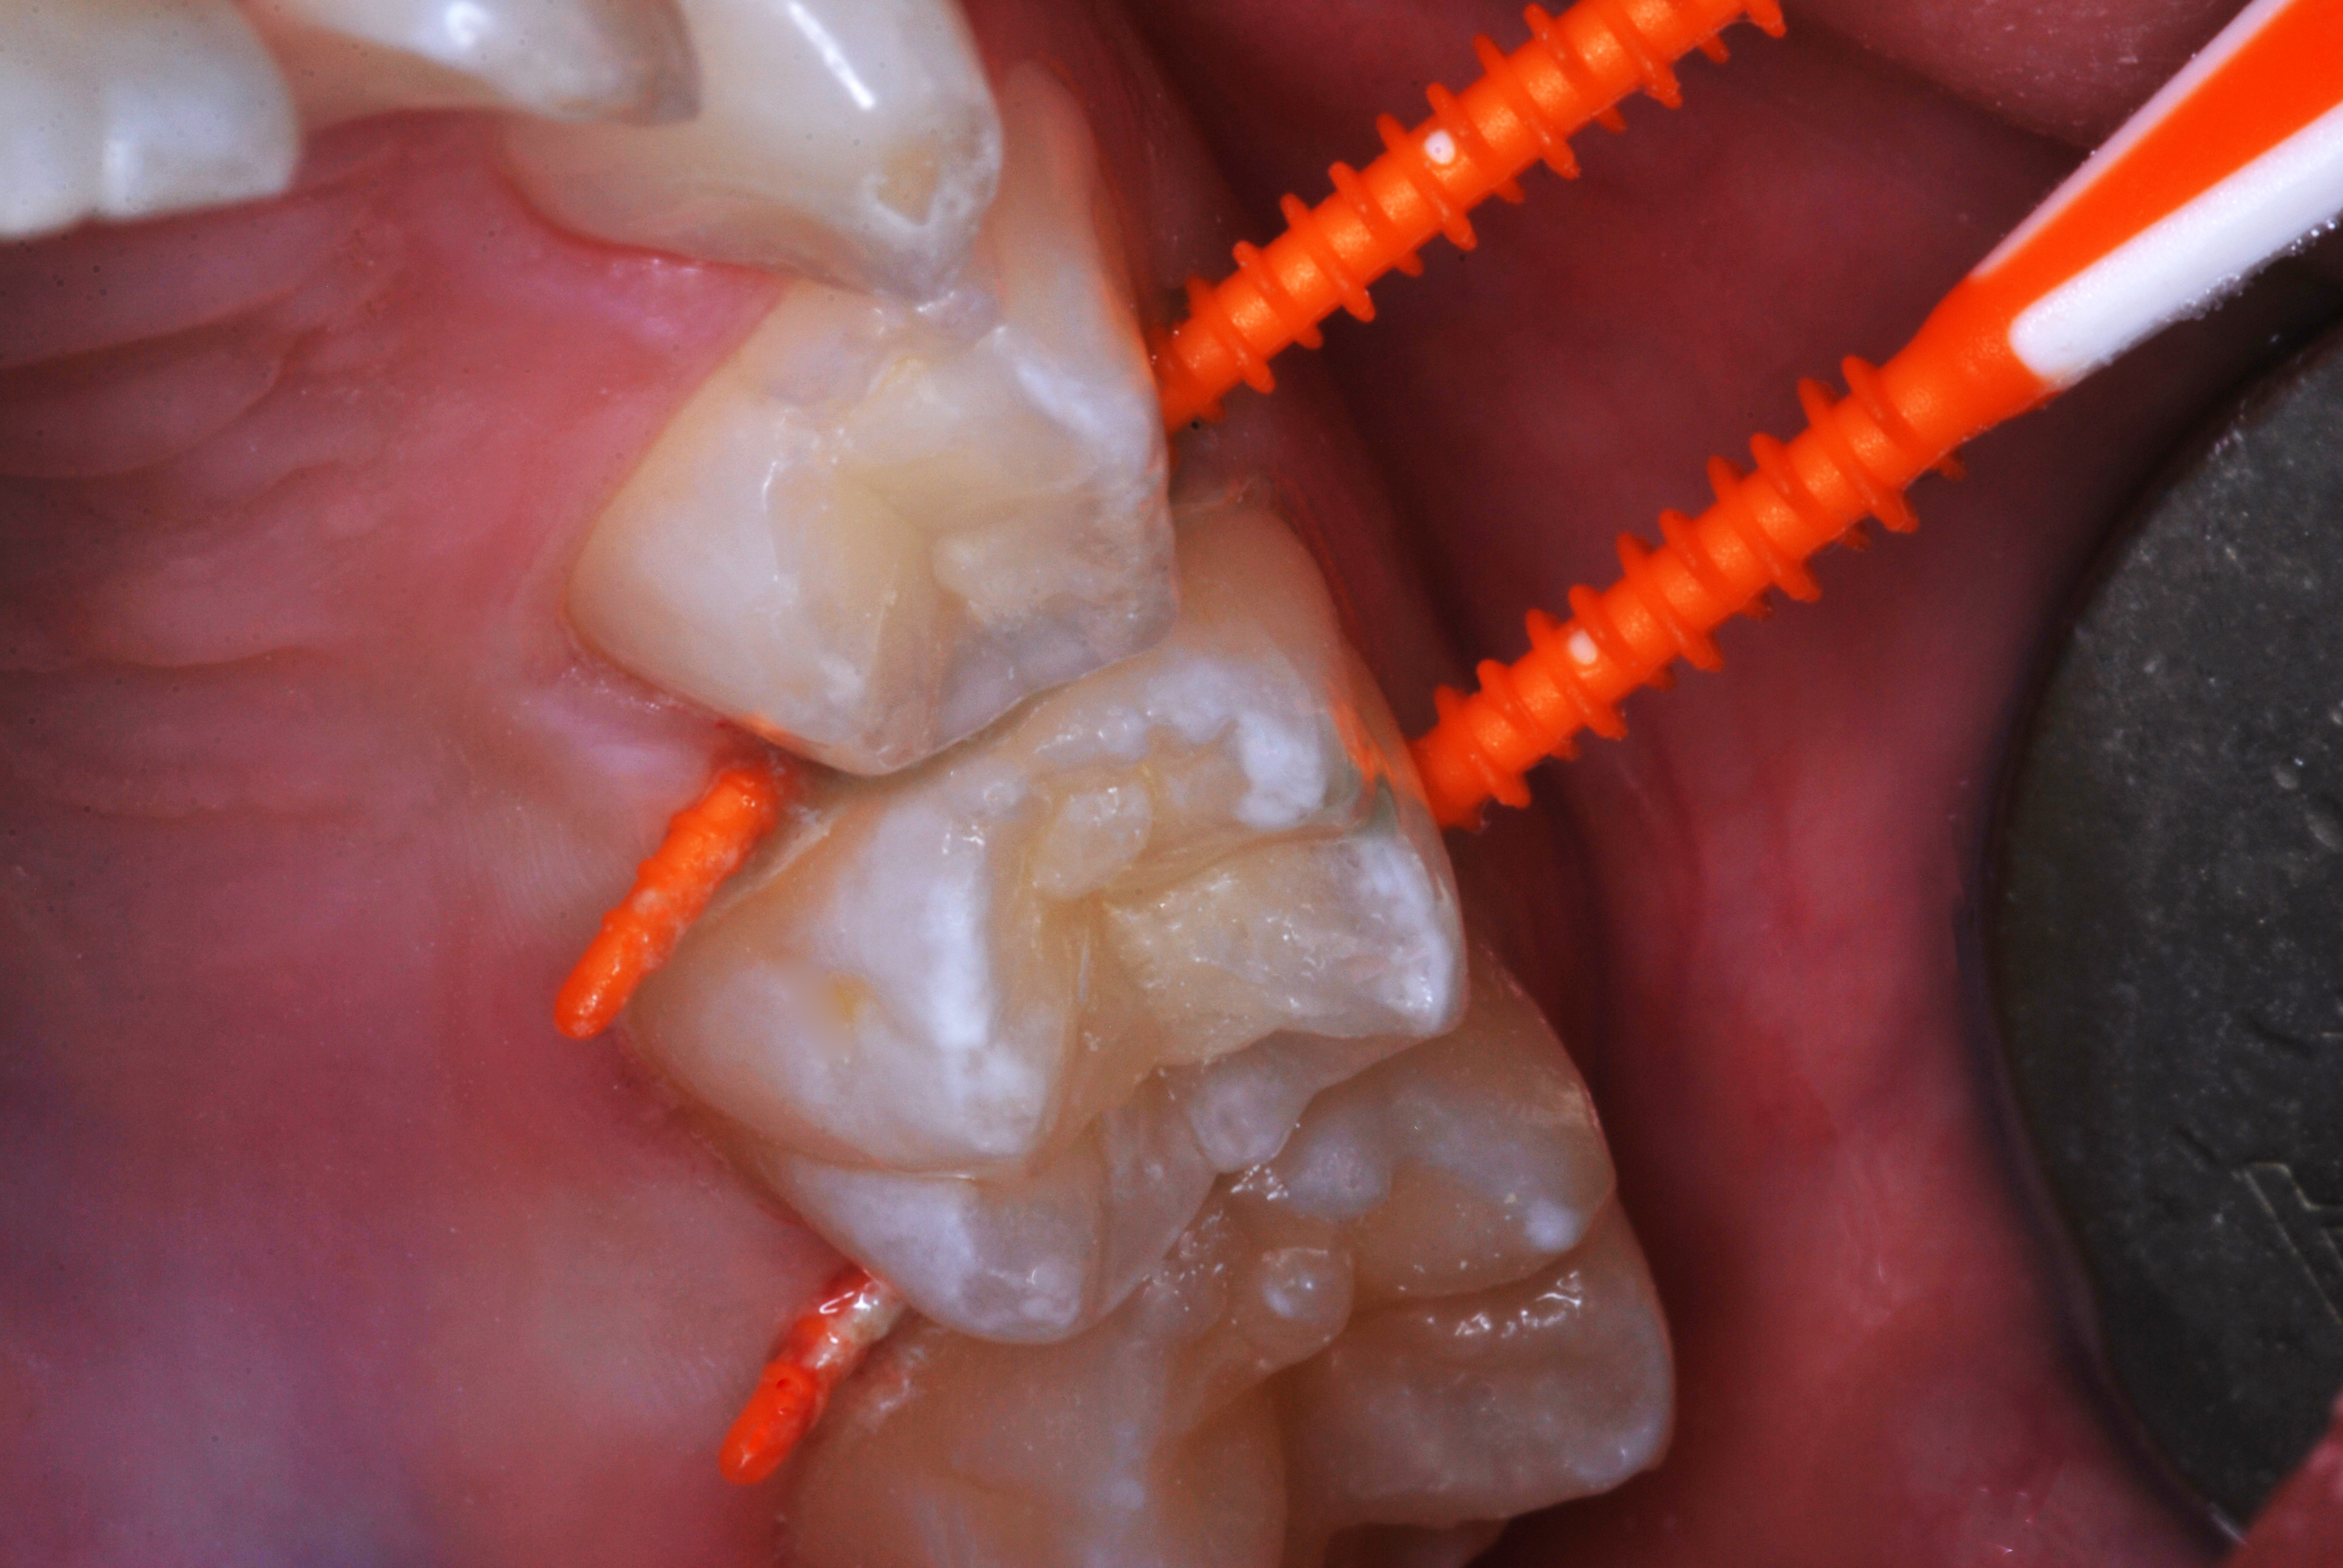

(20.) SDF proximal applications for small first and second molar caries lesions in teenage orthodontic patient, followed by preventive fluoride varnish cover of the area.

Figure 20

(21.) SDF proximal applications for small first and second molar caries lesions in teenage orthodontic patient, followed by preventive fluoride varnish cover of the area.

Figure 21